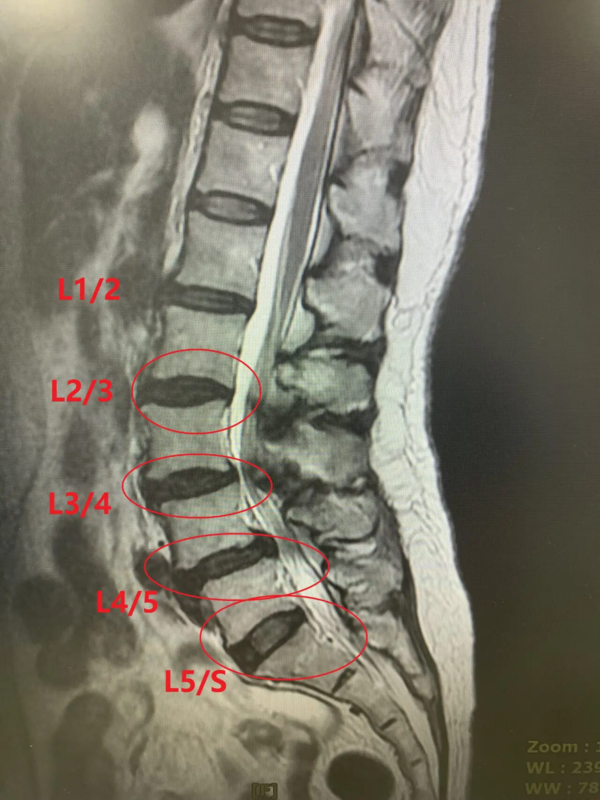

腰椎核磁影像显示腰椎多节椎间盘损伤,椎间盘厚度变薄。(椎间盘退行性病变と椎间盘突出)。并伴有椎管狭窄症

治疗了已经损伤的四节椎间盘(L2/L3、L3/L4、L4/L5、L5/S)可期待坐骨神经痛症状的好转。